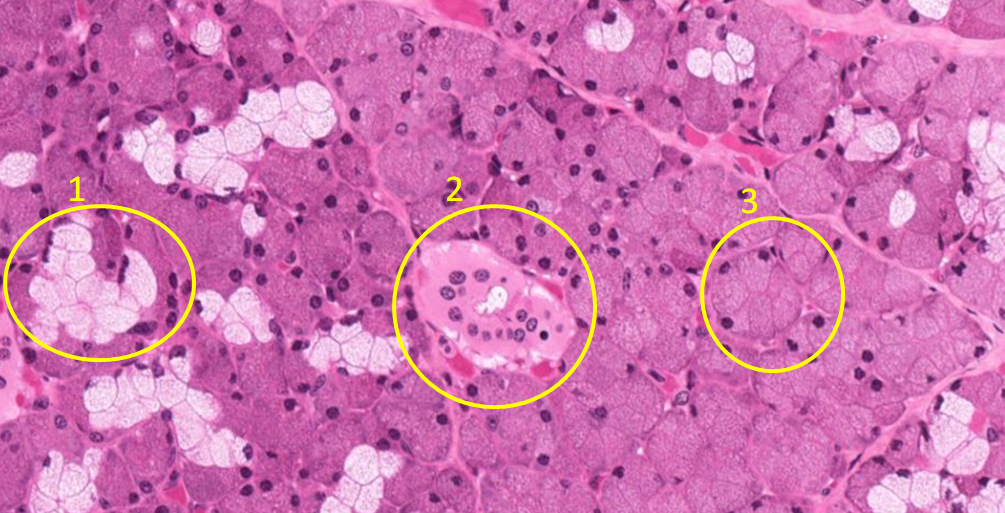

Glândulas exócrinas (1 misto; 2 ducto(epitélio cúbico simples; 3 seroso).